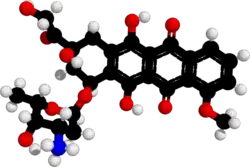

| Formula | C27H29NO11 |

| Molar mass | 543.525 g·mol−1 |

Doxorubicin (DXR) is a 14-hydroxylated version of daunorubicin, the immediate precursor of DXR in its biosynthetic pathway.

Doxorubicin interacts with DNA by intercalation and inhibition of macromolecular biosynthesis.[11][40][41] This inhibits the progression of topoisomerase II, an enzyme which relaxes supercoils in DNA for transcription.[42] Doxorubicin stabilizes the topoisomerase II complex after it has broken the DNA chain for replication, preventing the DNA double helix from being released and thereby stopping the process of replication.[11] It may also increase quinone type free radical production, hence contributing to its cytotoxicity.[15]

The planar aromatic chromophore portion of the molecule intercalates between two base pairs of the DNA, while the six-membered daunosamine sugar sits in the minor groove and interacts with flanking base pairs immediately adjacent to the intercalation site, as evidenced by several crystal structures.[39][43]